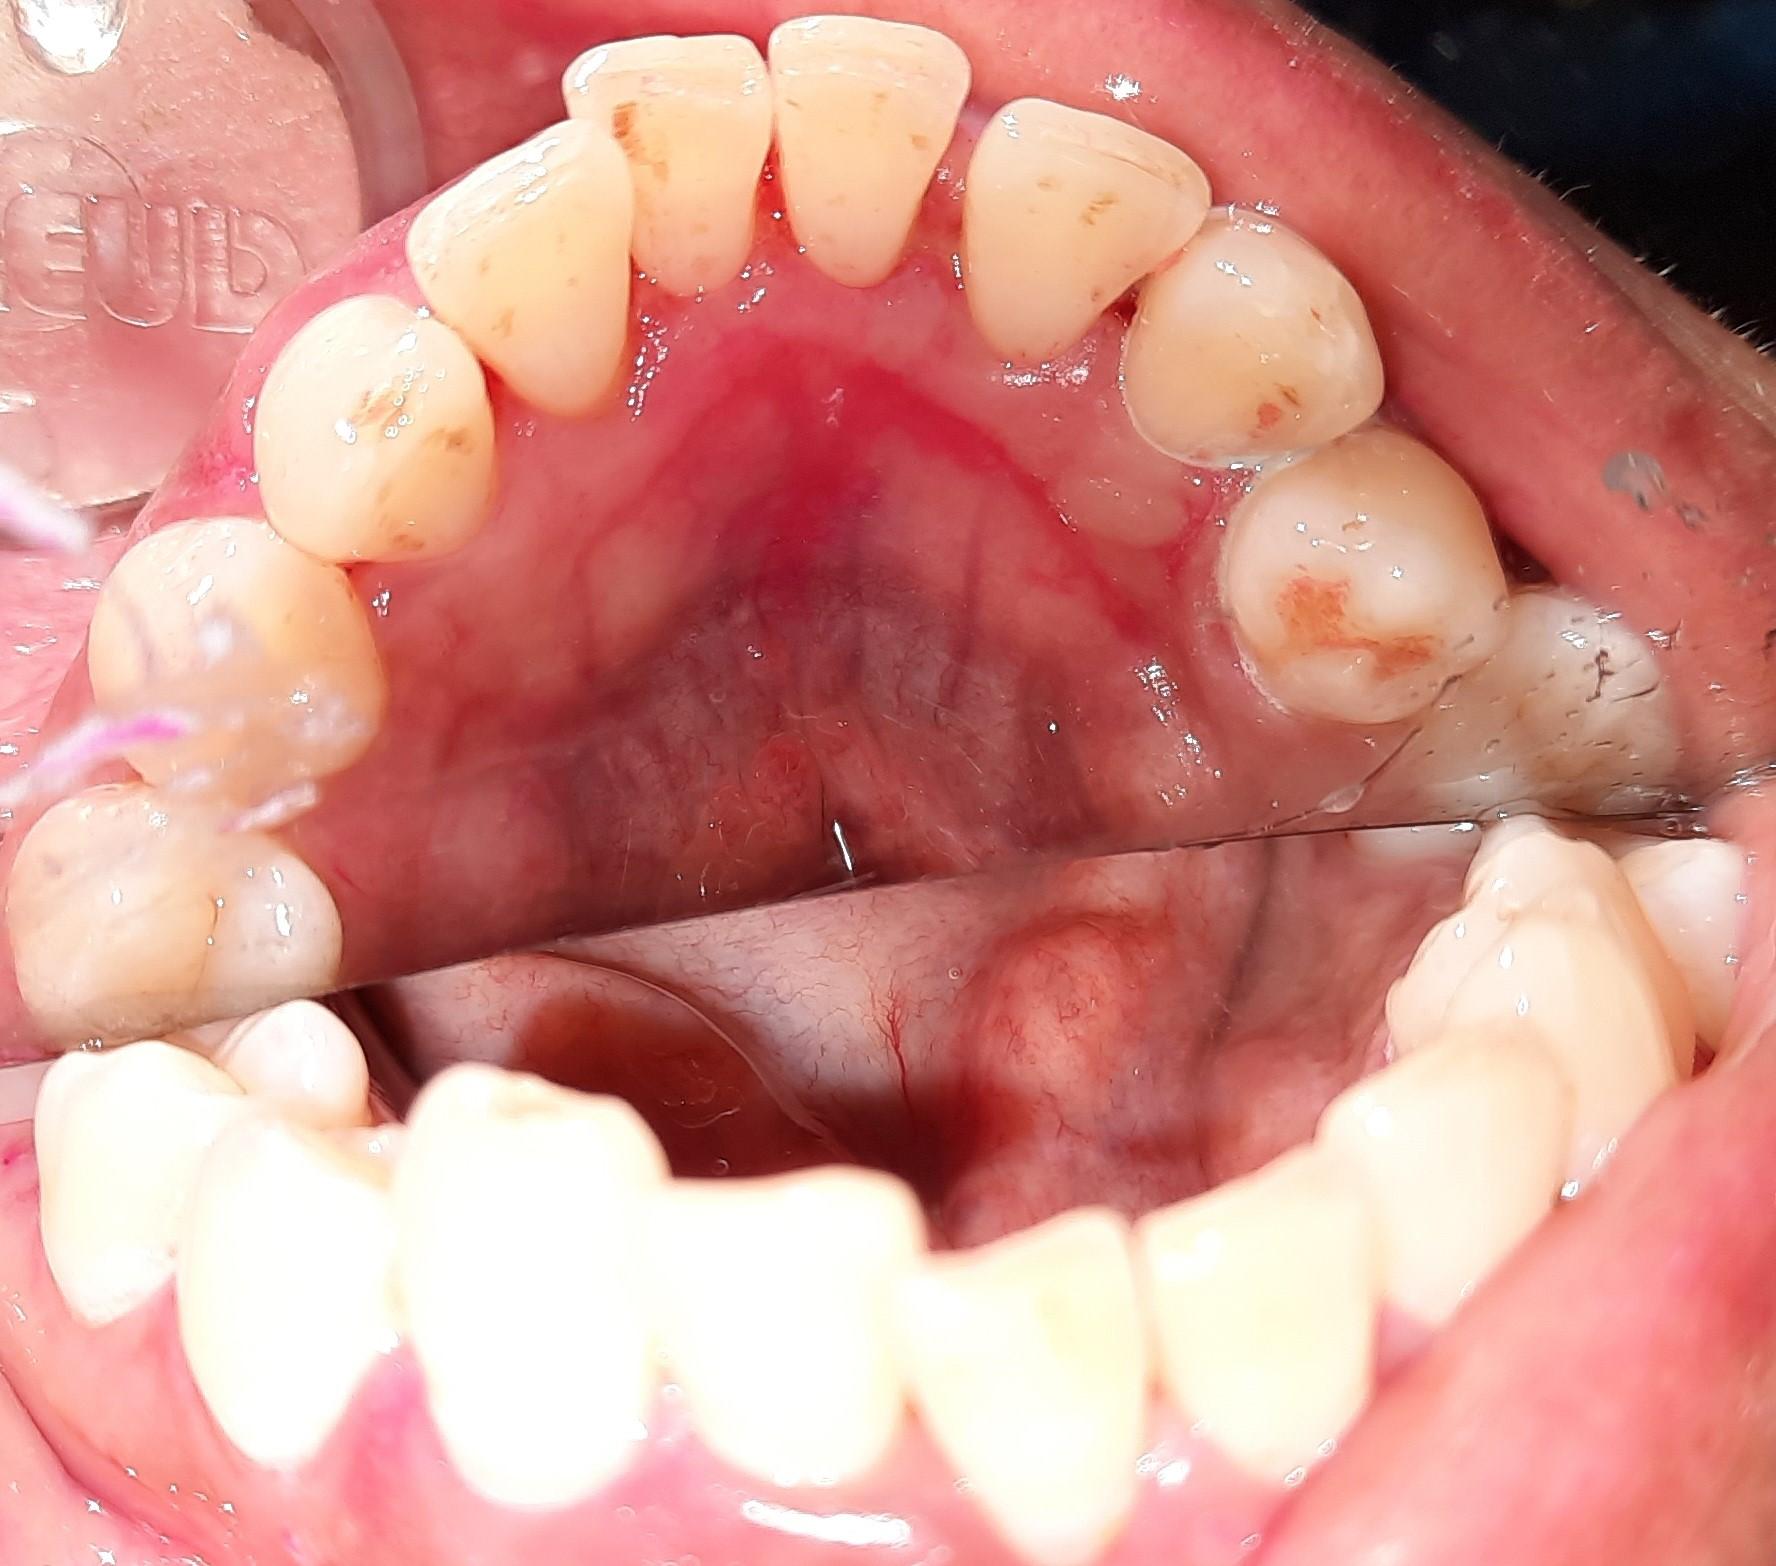

Discuss Dentistry » All Posts https://demo.discussdentistry.com/forums/forum/cosmetic-aesthetic-dentistry-2/feed/ Tue, 02 Sep 2025 00:41:25 +0000 https://bbpress.org/?v=2.6.11 en-US https://demo.discussdentistry.com/forums/topic/orthodontic-treatement-or-smile-redesigning/#post-26156 <![CDATA[Orthodontic treatement or smile redesigning]]> https://demo.discussdentistry.com/forums/topic/orthodontic-treatement-or-smile-redesigning/#post-26156 Mon, 12 Aug 2024 10:08:02 +0000 site_admin Dear all eminent orthodontists, Help required with this case.Female patient /Age…44 yrs / No relevant medical history

Patient came with a complaint of upper right central incisor drifting and  ” slightly coming outside.”  and it seems lower anteriors  have also tilted labially a little. This perhaps is due to gum recession and tartar accumulation.. The images shown below are after scaling.

What is the treatment?

Will orthodontic treatment work?  If yes can this case be done with aligners?

The local aligner company has suggested IPR of lower incisors and thereafter retroclination of U/L incisors. Is this possible or should I treatr the case with smile redesigning. The patient also wants other diastemas to be closed.  Hope to see a lot of responses and many thanks in advance for the same.